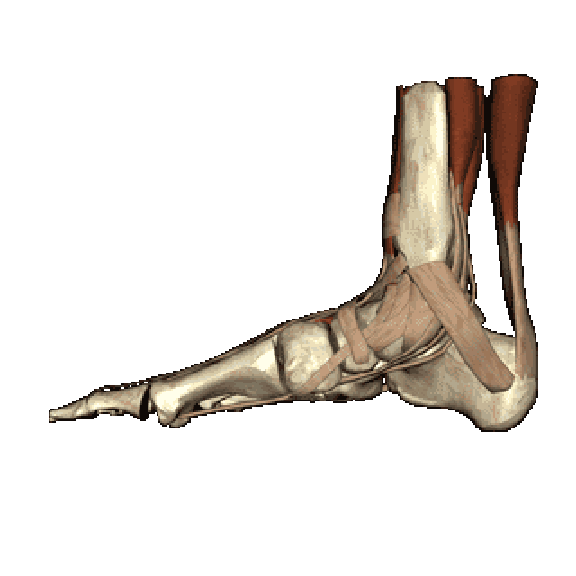

解剖及入路